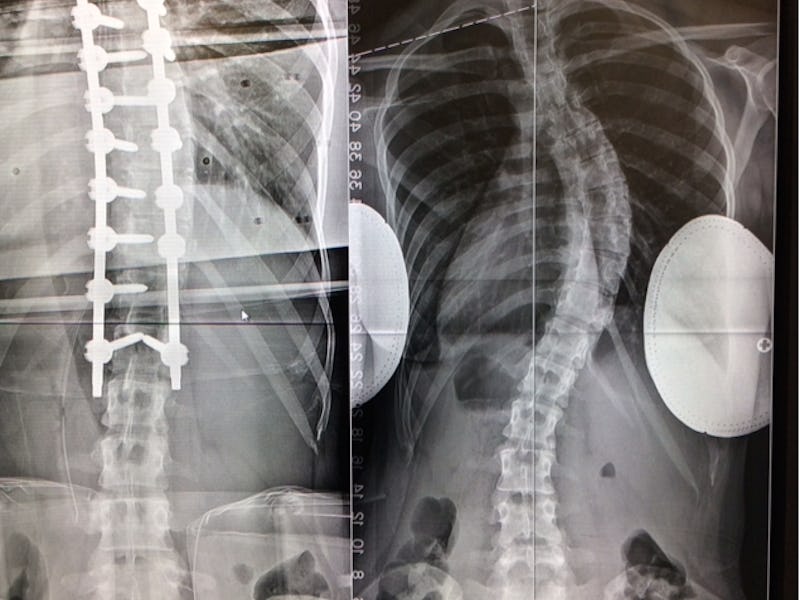

Two months into my recovery from back surgery, I couldn’t do much but lie uncomfortably still. Scoliosis curved my spine 20 degrees by the time I was 10 years old. Many people have curves of 8 to 10 degrees and live perfectly normal lives. 20 is the point at which doctors get concerned. Though I went through puberty in a back brace, my spine never got the message. In college, I had the wheeze — if not the casual cool — of the smokers, my unearned pack-a-day breathlessness a product of pressure from my vertebrae on my lungs. By the time I graduated, my curve was 58 degrees.

The situation needed fixing, so I went to a surgeon who described his plans to suit me up like Wolverine. He’d cut me open neck-to-waist and bring my spine in line with titanium rods. My doctor gave me pamphlets about the procedure and recovery, but I ignored them out of a stubborn refusal to acknowledge that this was happening.

Me pre-surgery. I'm not leaning -- that is what standing straight looked like

The before (right) and after (left)